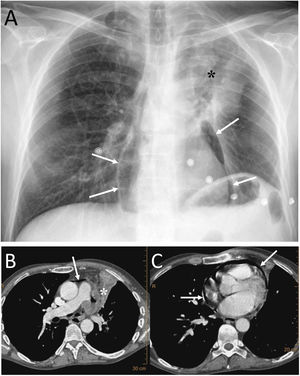

Pericardial locationPneumopericardium (PPC) is caused by invasive procedures (thoracentesis, endotracheal intubation, thoracotomy, etc.), pericarditis, chest trauma, barotrauma and fistulas with air-borne structures (bronchial tree, gastrointestinal tract, and pleural or peritoneal spaces).19,20 In pneumothorax and PM due to barotrauma or blunt trauma, it has been suggested that the aetiopathogenesis could be the rupture of the alveolar walls with air passing towards the hila and/or the pleura, dissecting the peribronchovascular space. If this air spreads around the pulmonary veins and arteries, it can reach the pericardium. Another possible cause of air in the pericardium in chest trauma would be direct communication with the pleura or tracheobronchial tree through a pericardial rupture or tear.19 Most cases of PPC are due to iatrogenesis or trauma, spontaneous PPC being very rare.20 In the case of pulmonary neoplasia (Fig. 7), the possible routes are: direct invasion of the necrotic tumour that causes a bronchopericardial fistula, trauma due to bronchoscopy or thoracentesis, and rupture to the pericadium of a focus of necrosis.20

A 53-year-old man with squamous cell carcinoma of the lung presented with chest pain, fever and productive cough. A) The chest X-ray showed a lung mass in the left upper lobe (black asterisk) and pneumopericardium (white arrows). B and C) Computed tomography showed progression of the upper left lung mass (asterisk) and pneumopericardium secondary to the direct extension of the tumour to the pericardium (white arrows).

It must be remembered that: chest X-ray shows air around the cardiac silhouette, limited superiorly by the lower border of the aortic arch, without extension around the trachea, bronchi or cervical region. CT enables confirmation of the diagnosis and identification of the possible cause. Treatment will be conservative if the pneumopericardium is small and the patient is stable and asymptomatic.21